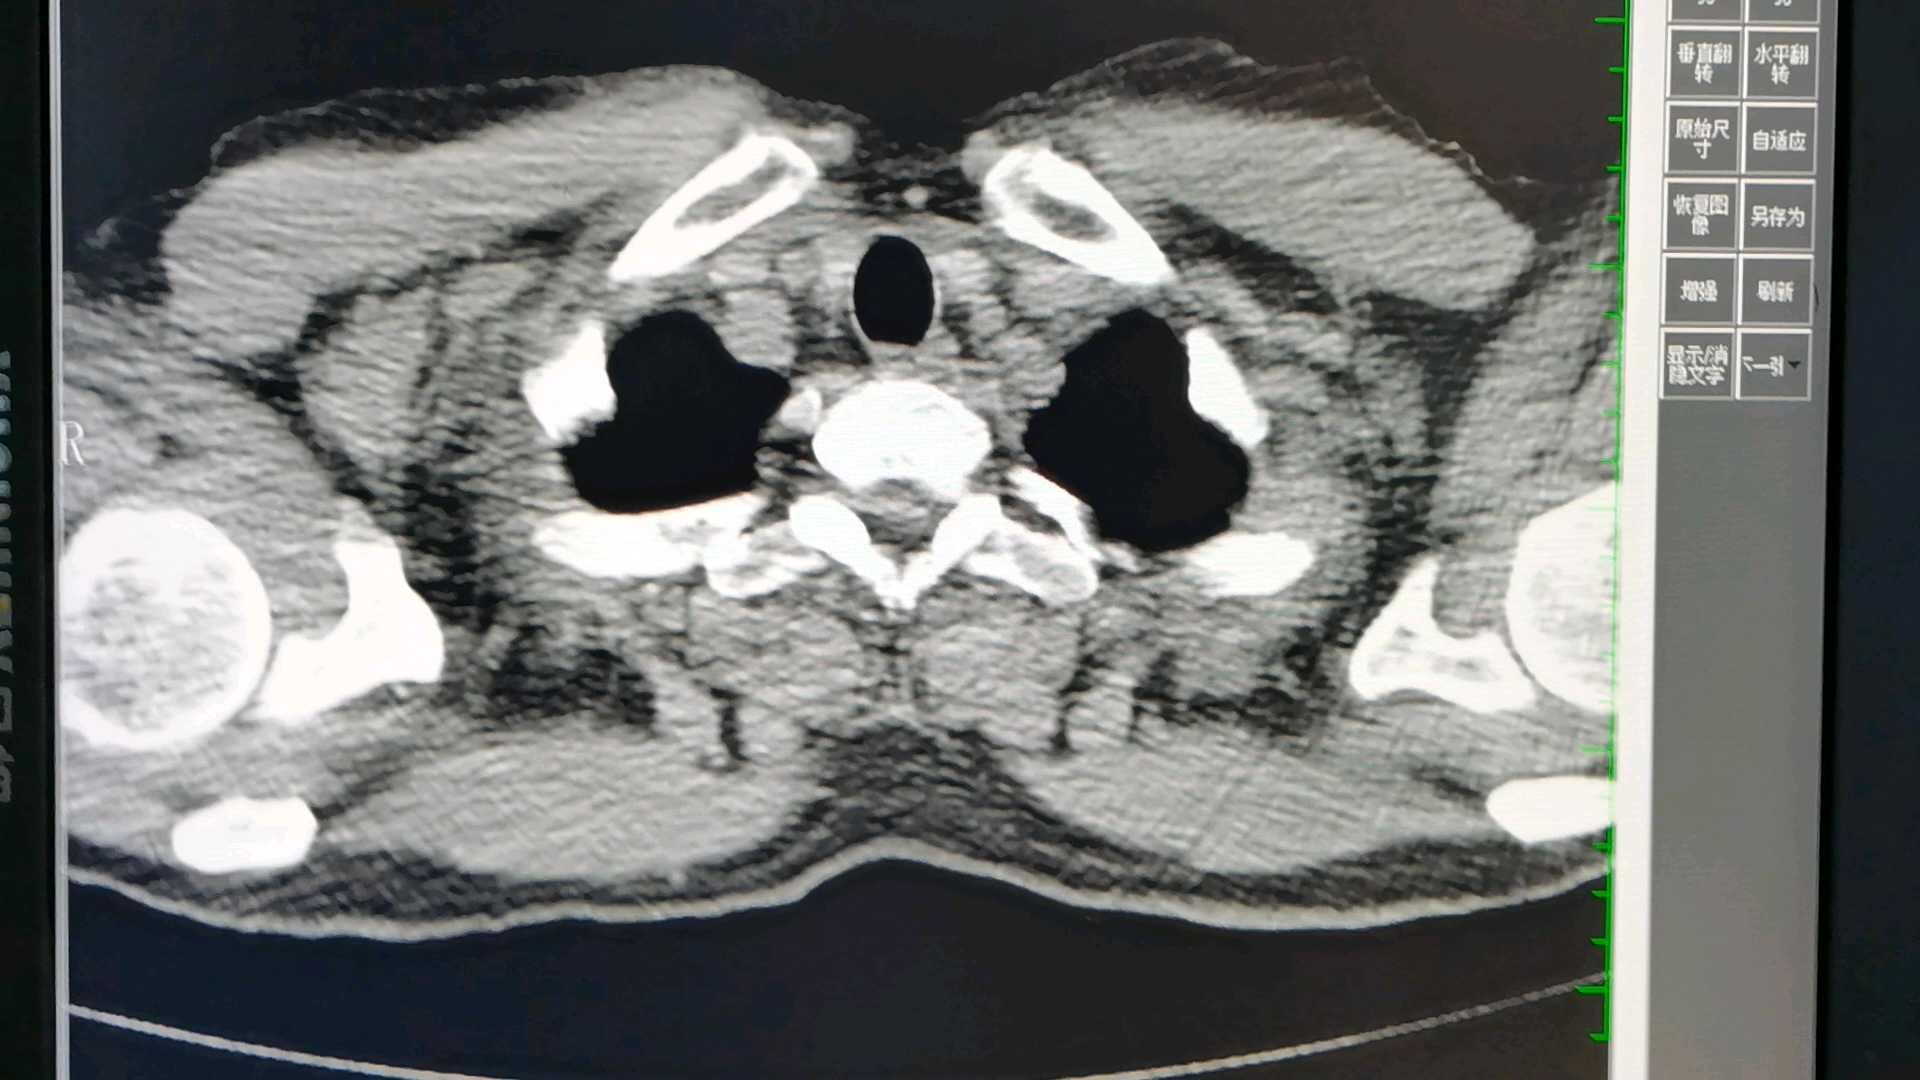

病例男,48岁

正常体检,也是一个电话明确诊断。